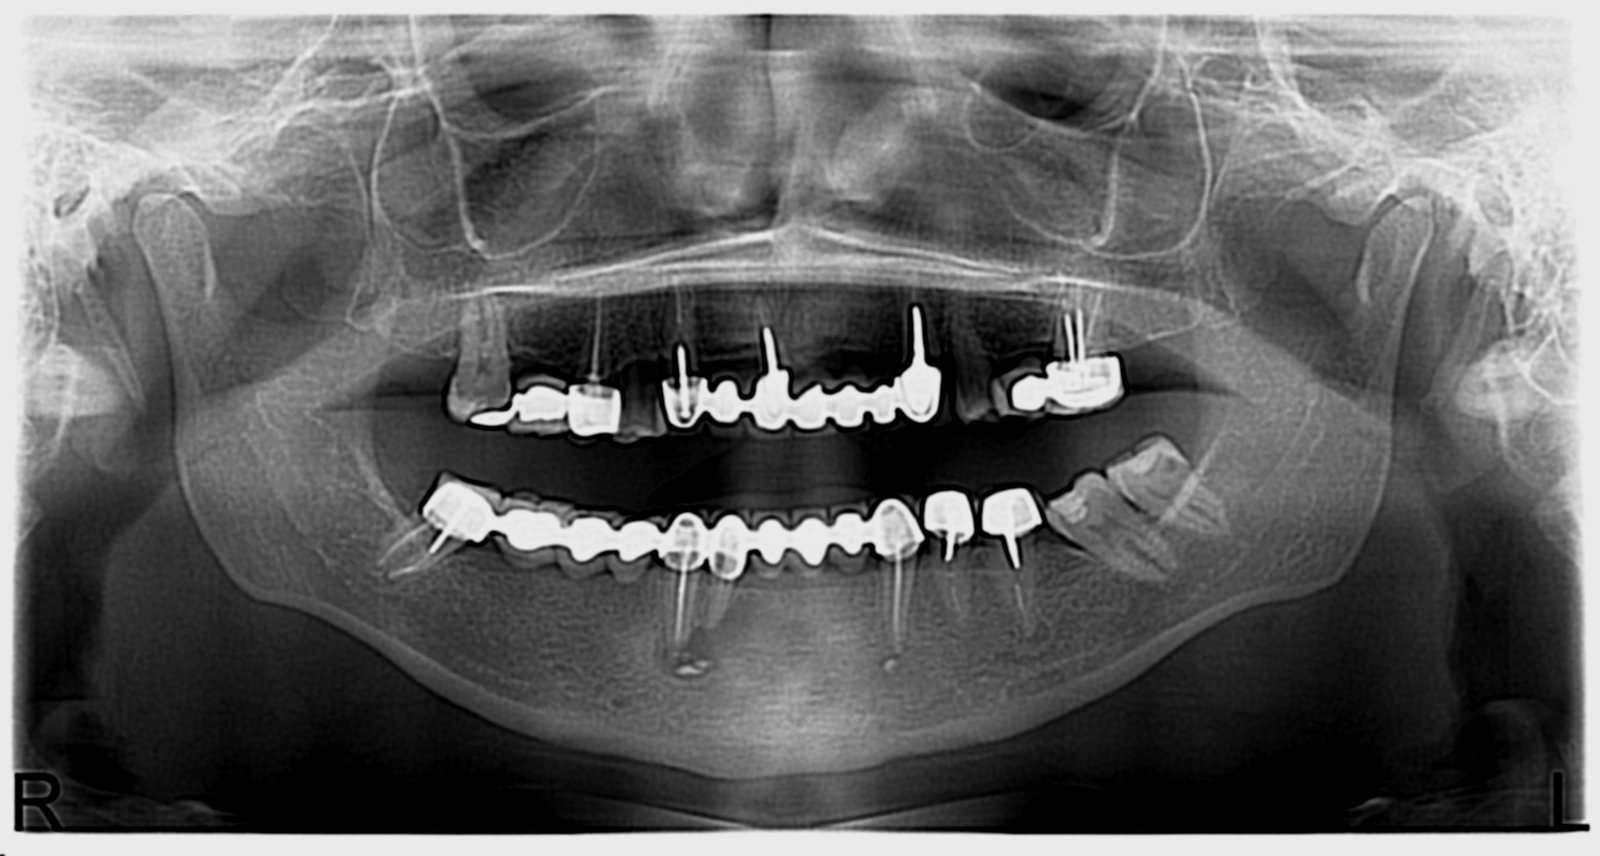

Réhabilitation complète avec mise en charge immédiate (4 implants bas / 6 implants haut)

Le patient se présente avec des dents qui bougent, en haut et en bas.

Nous avons commencé par la mâchoire inférieure avec 4 implants et une mise en charge immédiate.

Trois mois après, le haut a été fait avec le même principe avec 6 implants.

Cette fois-ci, il existait un déficit osseux, résolu par une technique d’expansion sans avoir recours à la greffe d’os.

Les prothèses réalisées sont vissées, ce qui permet de les enlever, les nettoyer une fois par an, ou résoudre n’importe quel problème.